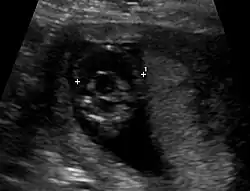

- semilobäre Holoprosencephalie (teilweise Trennung, hinterer Interhemisphärenspalt mit rudimentären Hemisphären, ein Hirnventrikel)[14]

Die Diagnose kann vorgeburtlich im Rahmen von Pränataldiagnostik durch insbesondere Feinultraschalluntersuchungen im zweiten Trimenon, teils aber auch schon früher, gestellt werden. Während die Feststellung der alobären und der semilobären Form oft recht einfach ist, ist die der lobären Holoprosencephalie komplizierter.

Nachgeburtlich sind die Schnittbildverfahren Sonographie und Magnetresonanztomographie Methoden der Wahl.[19]